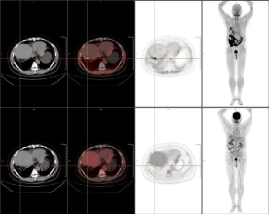

例二:79岁老年女性,胆囊结石7年,现反复腹痛待查,临床高度怀疑胰腺癌。传统影像学检查未能明确病灶边界与转移范围,通过18F-FAPI PET/CT显像,确诊为肝左外叶肝内胆管细胞癌(ICC),左侧锁骨旁、纵隔内(4R、4L、5、6、7)及双侧肺门、腹腔内、肝胃间隙、腹膜后、腹主动脉左旁、盆腔内多发淋巴结转移灶,胰腺及腹主动脉受侵。

新型分子探针18F-FAPI清晰呈现了原发灶及转移灶的精准位置、大小及周围组织侵犯情况,同时发现了隐匿的转移灶,为临床制定个体化治疗方案提供了关键依据。为肿瘤患者病灶的精准识别带来福音,为临床及时调整治疗策略、改善预后创造了条件。